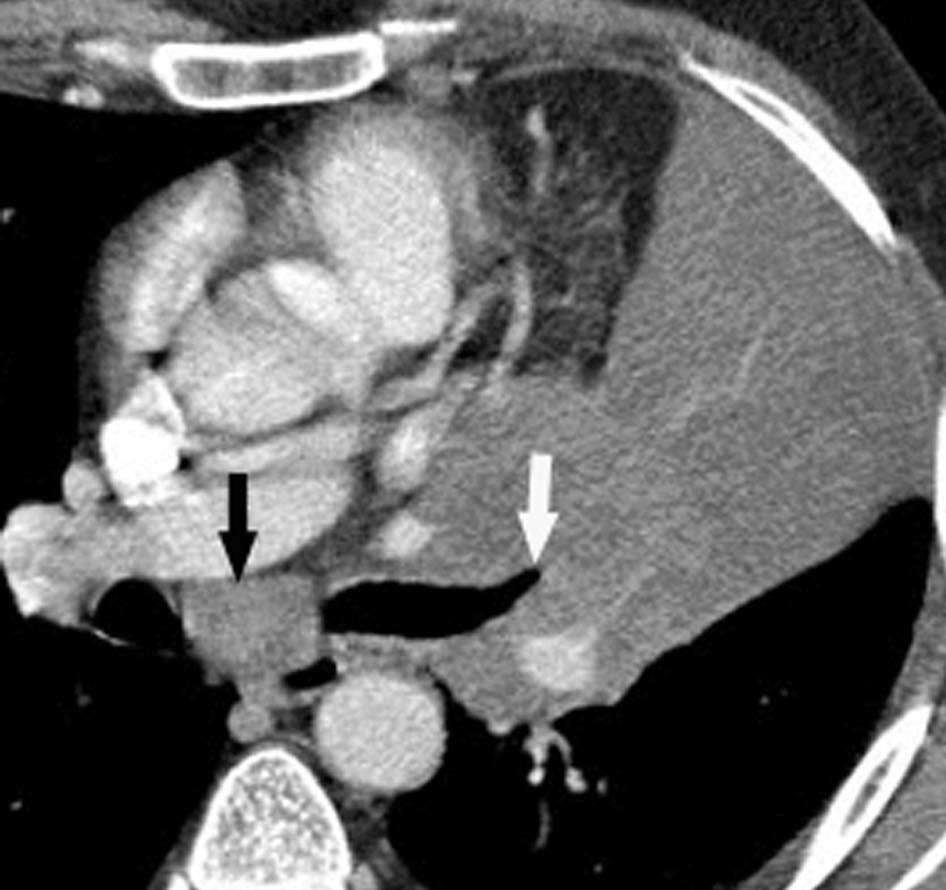

Fig. 11.--N2. (A) Corte axial de tomografía computarizada (TC) con contraste. Nódulo heterogéneo en el segmento 6 del lóbulo inferior derecho con infiltración de la vena pulmonar inferior (flecha). (B) En la reconstrucción de volumen se ponen de manifiesto la infiltración tumoral de la vena pulmonar (flecha negra), la adenopatía hiliar (asterisco) y una adenopatía calcificada lobar superior derecha (flecha blanca).